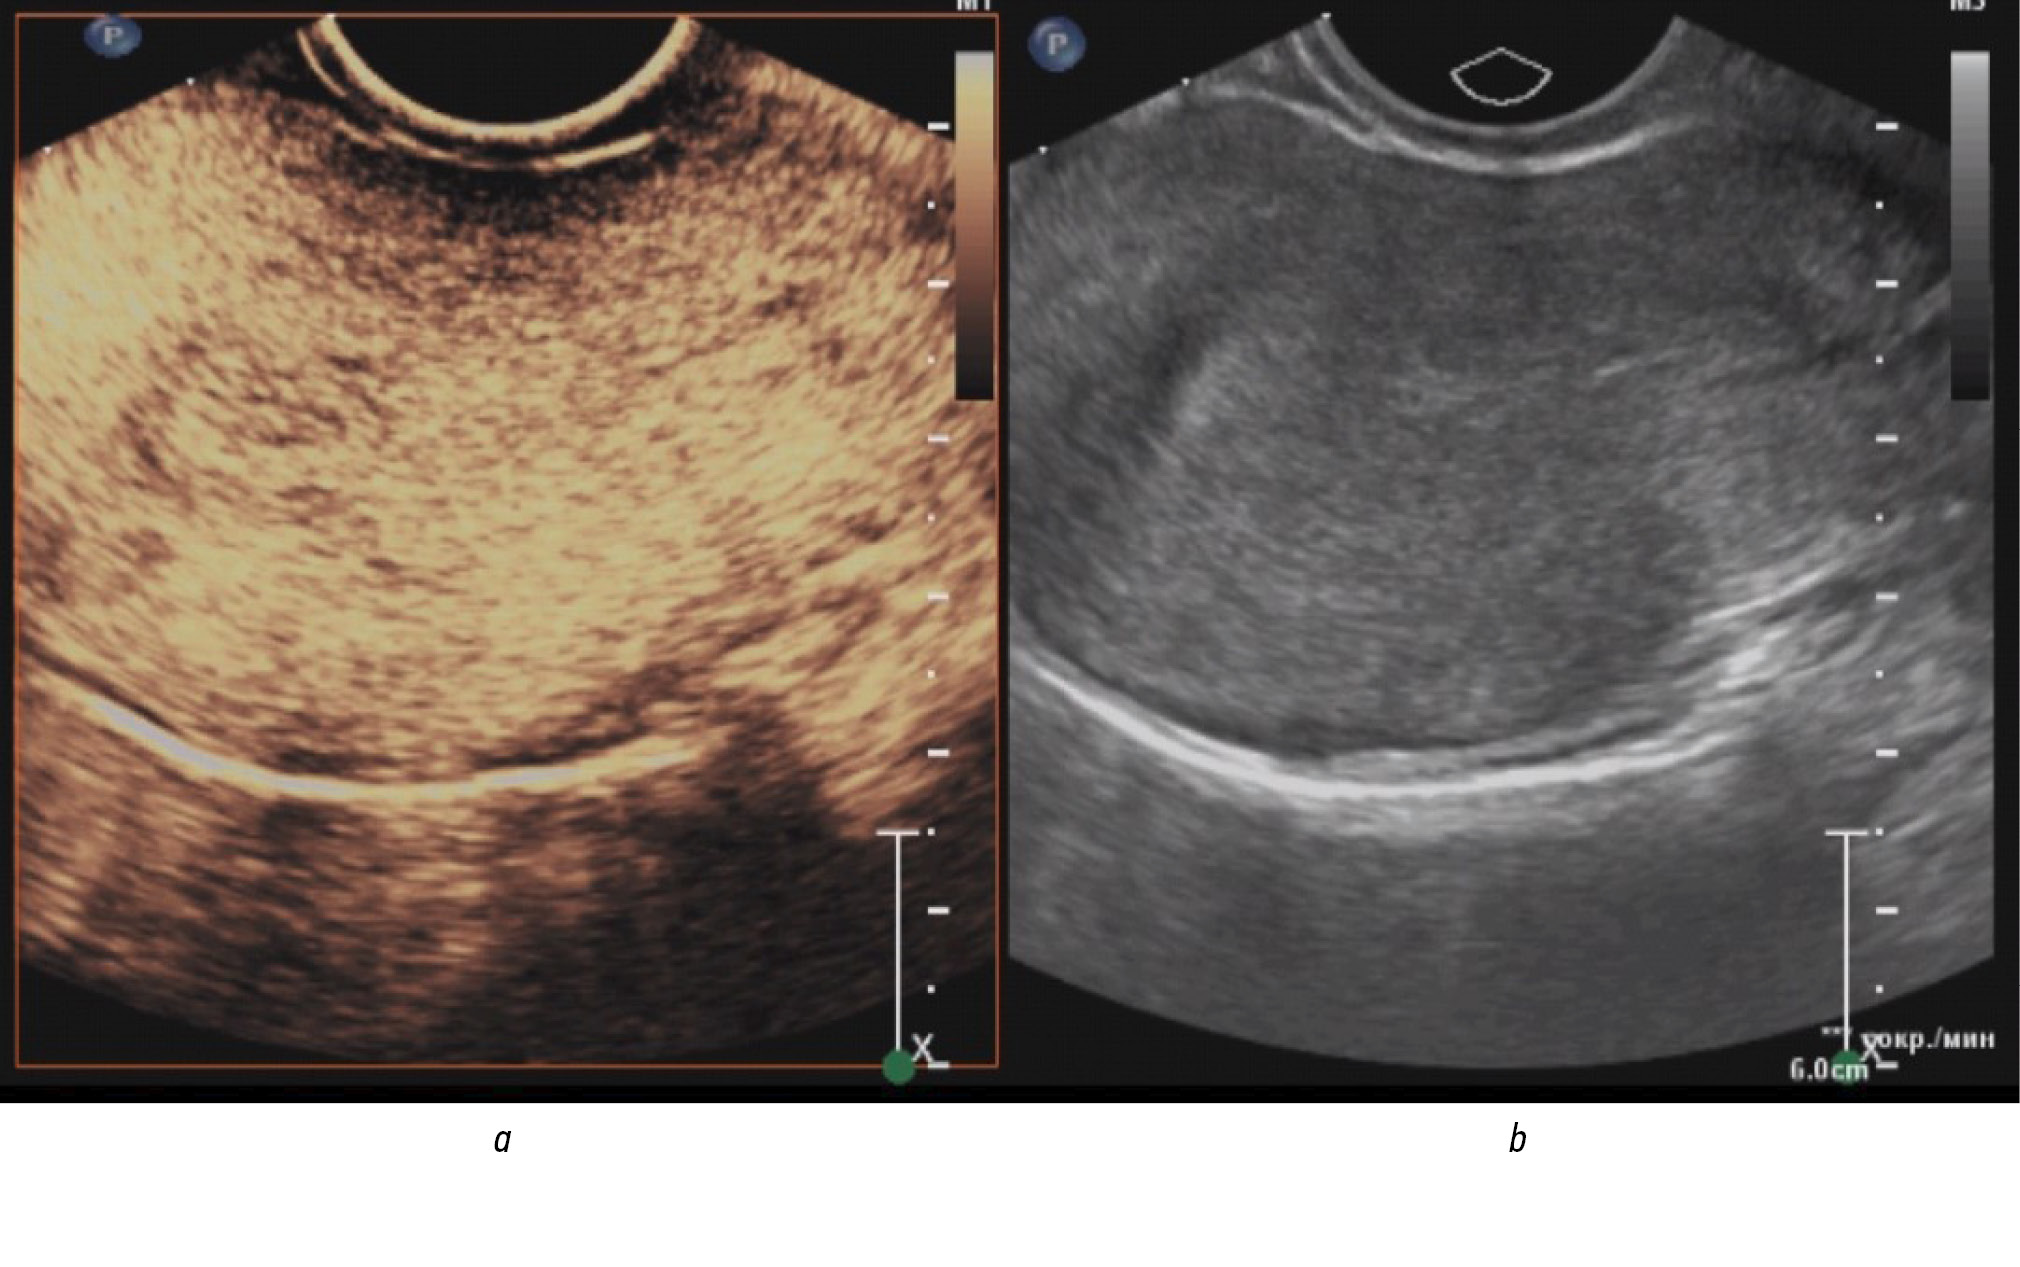

According to our study data (Tables 1 and 2), qualitative signs of contrast enhancement for endometrial cancer are homogeneous contrasting (71.1%), isocontrasting in the arterial phase (81.6%), and hypocontrasting in the venous phase (76.3 %), predominantly simultaneous entry of contrast agent compared with the intact myometrium (79.0%) and its earlier washout (71.1%) (Figs. 1 and 2). The time of the contrast agent entry into the site of endometrial formation, assessed visually by a specialist, varied from 8 s to 24 s from the start of the study (average, 15.16 s; median, 14.5 s).

Fig. 1. Arterial phase of contrast in endometrial cancer (homogeneous iso contrast without clear contours): a ― in contrast mode; b ― in the gray scale mode.